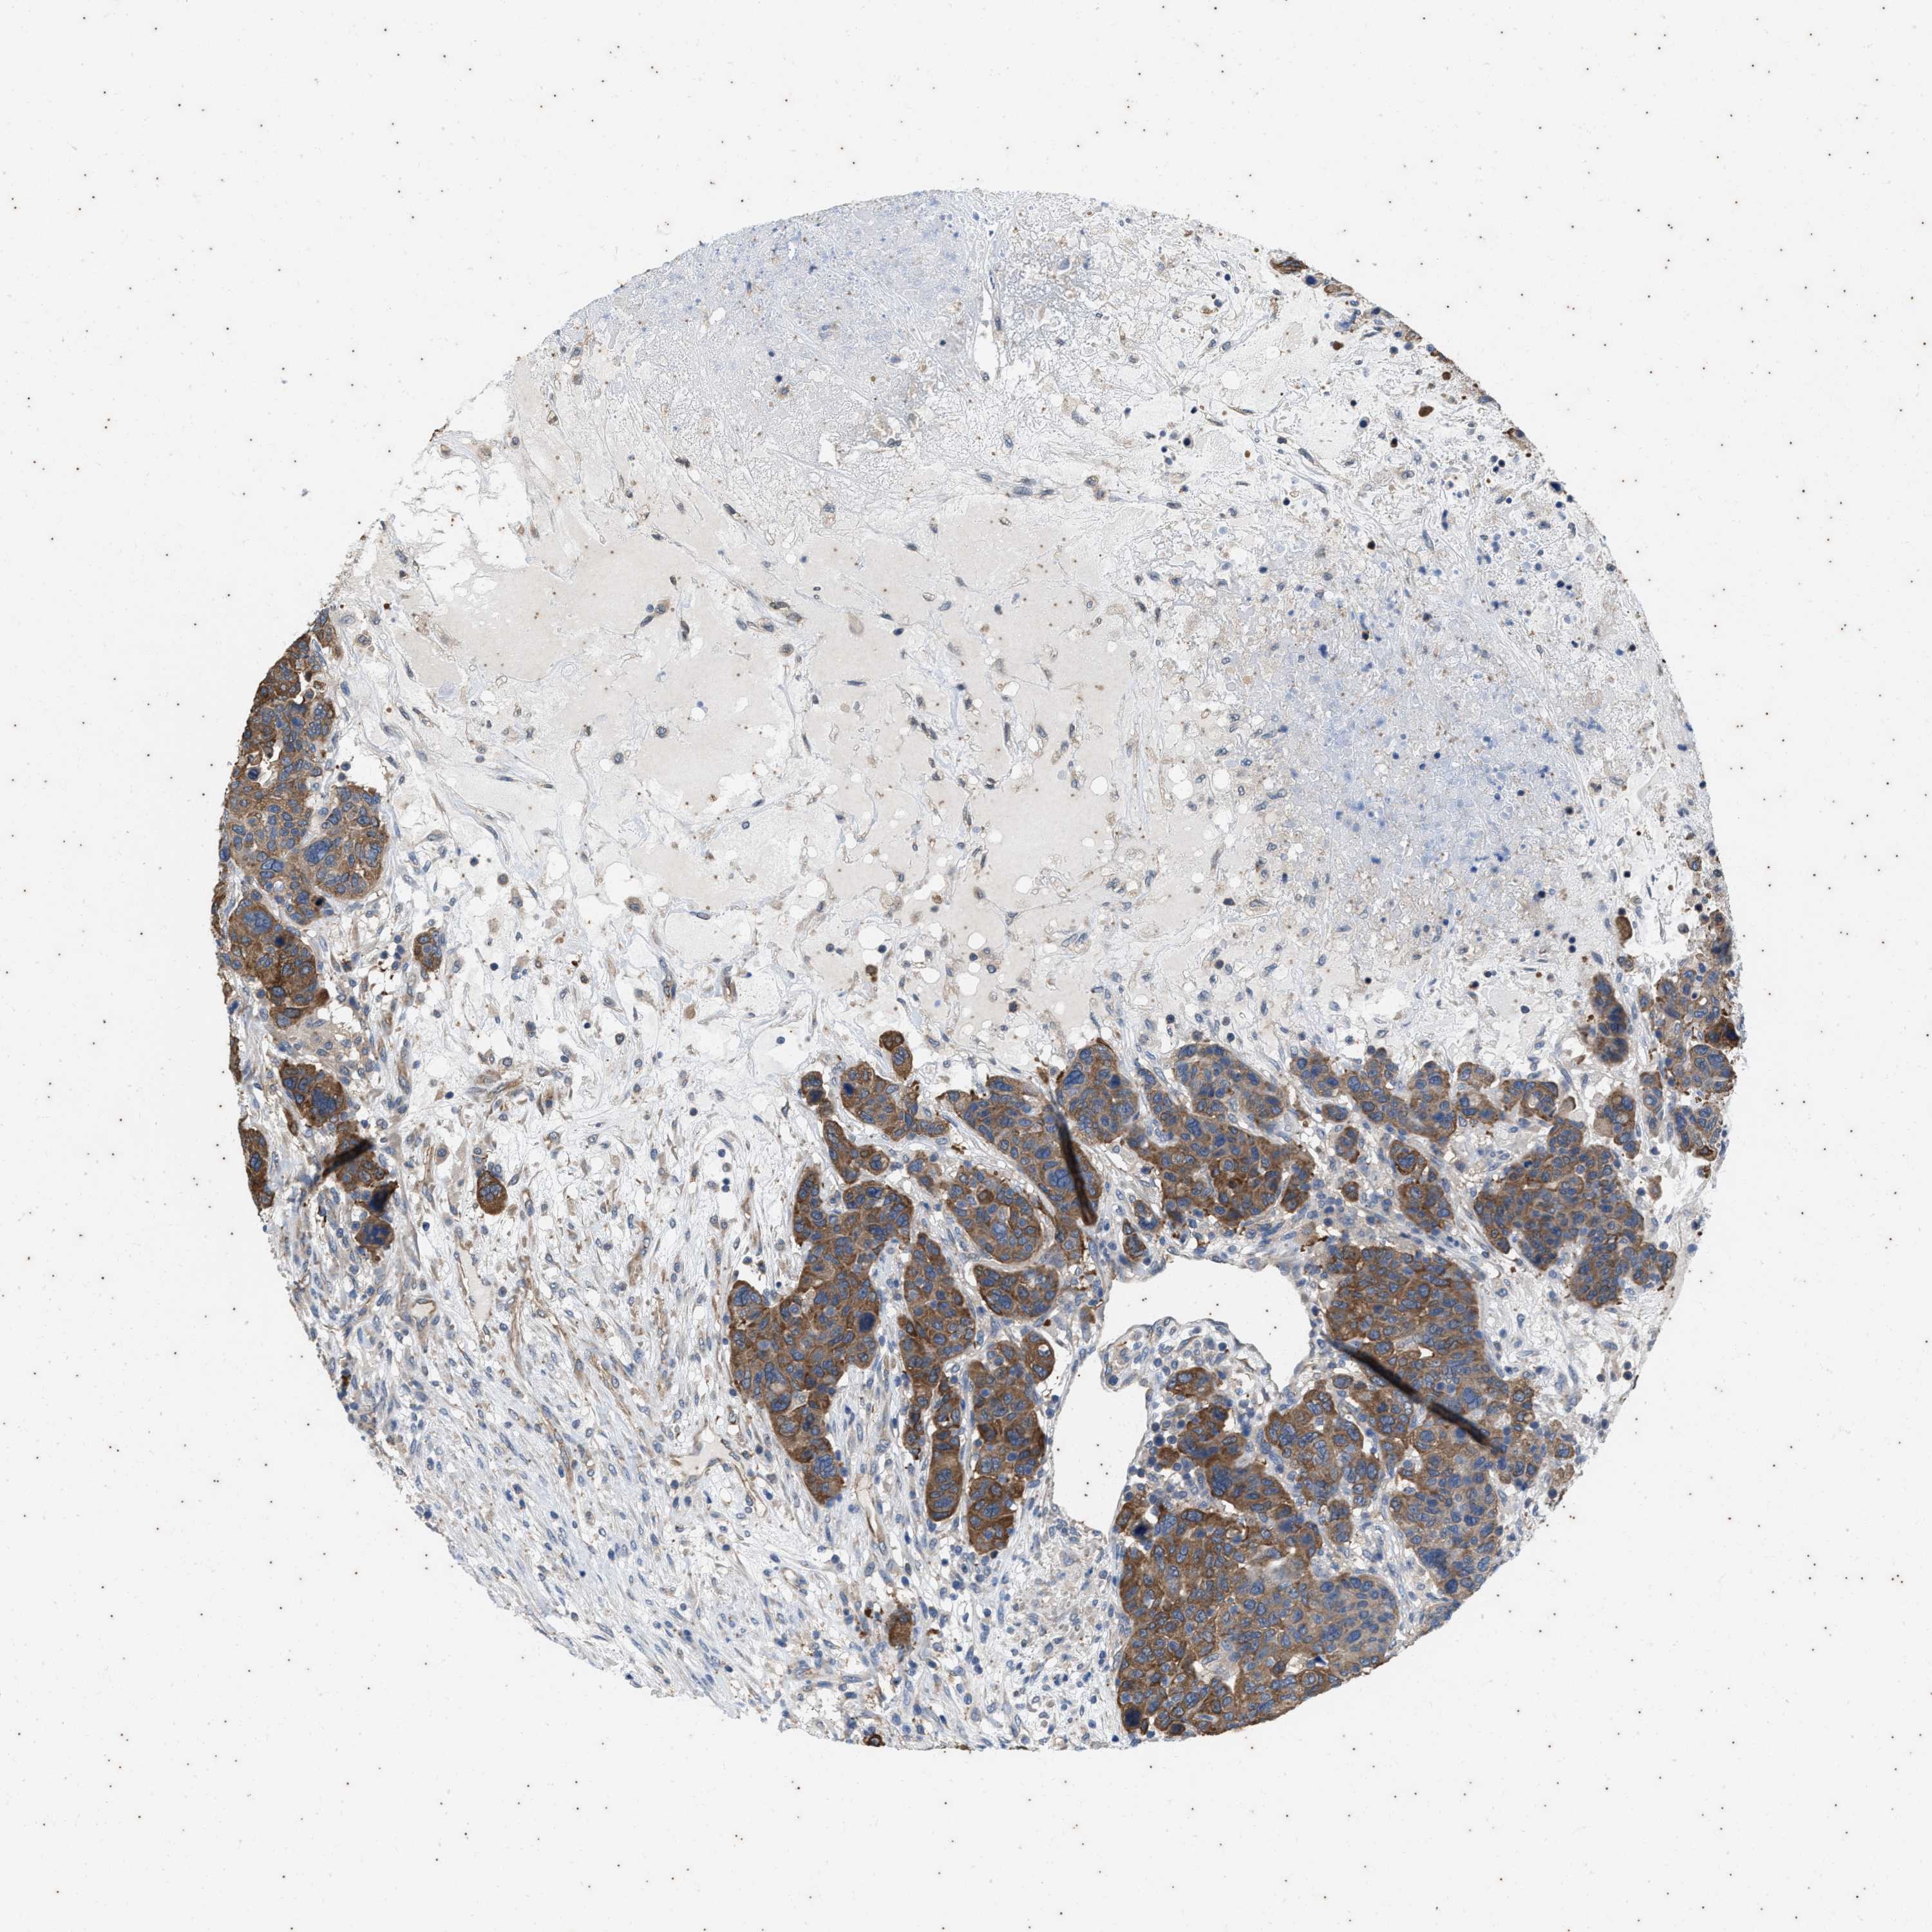

CANCER BREAST CANCER Show tissue menu

BRCA TCGA BRCA VALIDATION PROTEIN EXPRESSION